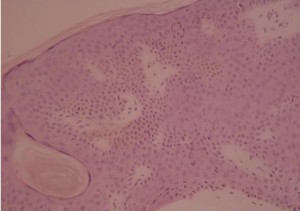

E. Irritated (activated)

{Wade, 1979} The epidermis contains epidermal nests called squamous eddies{Pierson, 2003}. The cells are intensely eosinophilic and are disposed in an onion peel fashion {Kao, 2000}. Indeed, this reaction would represent an immunological reaction{Berman, 1980; Berman, 1982} against SK lesions which leads the basaloid cells to convert into squamous-like cells. Squamous eddies, as well as the basal part of SKs, contain apoptotic cells Pesce, 2000}.The keratinocytes in the squamous eddies (or elsewhere?) are increased in size {Pesce, 2000}. Discrete to moderate atypia and mitotic cells, in contrast with other types may be present.

F. Inverted follicular keratosis (follicular poroma, basosquamous cell acanthoma)

This belongs to the irritated SK subtype. It shows contrary to “classical” irritated SK an endophytic pattern of growth.

{Pierson, 2003}Histologically it resembles irritated SK. Squamous eddies are present, but they sometimes keratinize in their center. What is different, is that there is a bulb like endophytic proliferation of eosinophilic keratinocytes, which have a basaloid or squamous-like morphology. The lesion is bordered by basaloid cells arranged in a palissade manner.